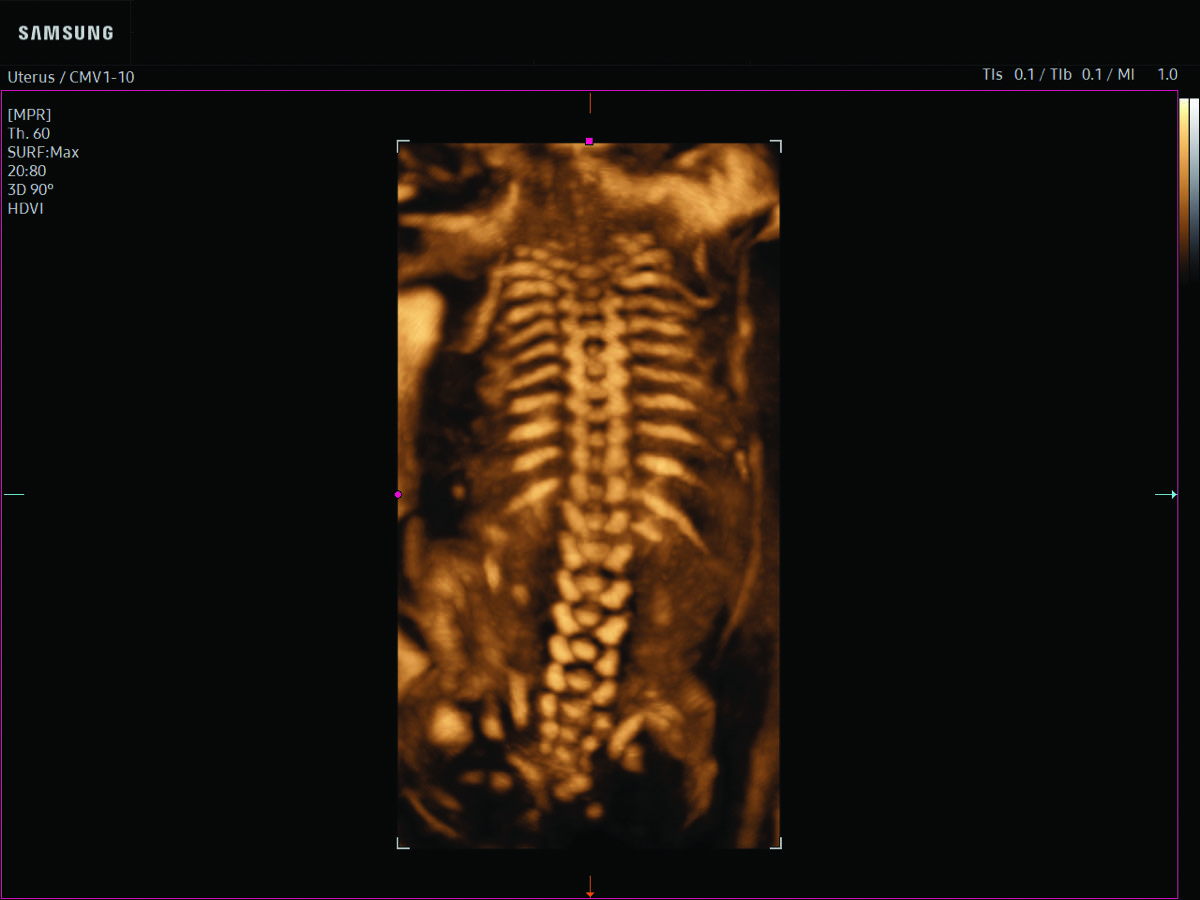

Comprehensive, advanced and expert MFM care for high-risk pregnancies

- Neural tube defects

- Fetal anomalies